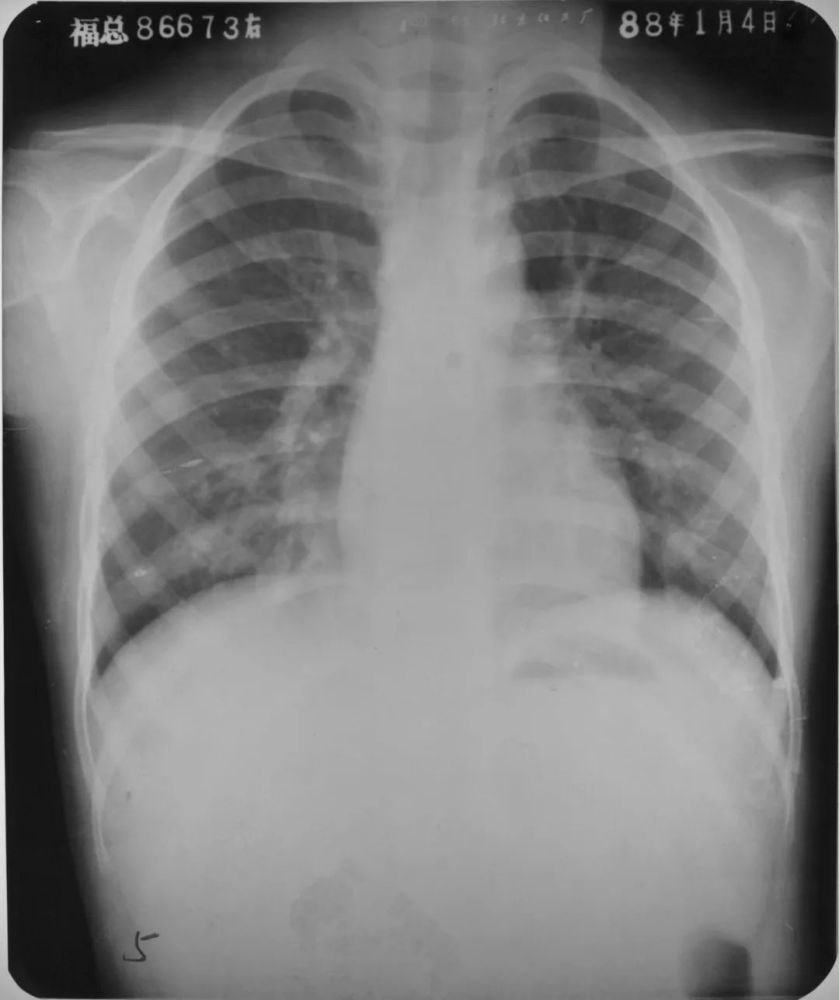

毛细支气管炎胸片

两下肺支气管肺炎胸部正位片示:两肺多发不规则的小片状或斑片状边缘